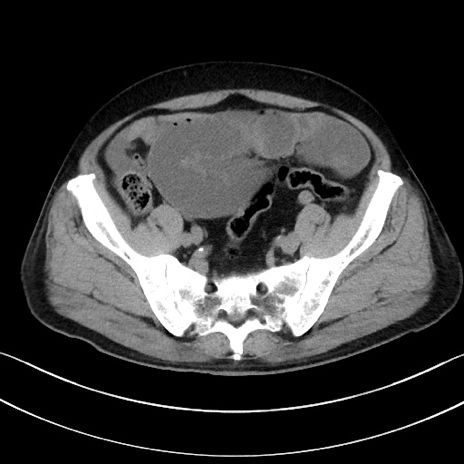

冠状断像

【症例】70歳代男性

【主訴】腹痛

【現病歴】今朝から腹痛あり。全体的に痛い。特に左上の方。排ガスが今日はない。冷や汗が出る。

【既往歴】直腸癌術後

【身体所見】左側腹部〜上腹部に圧痛あり。腹膜刺激症状明らかなではない。軽度反跳痛。左下腹部に術後瘢痕あり。

【データ】WBC 7700、CRP 0.02